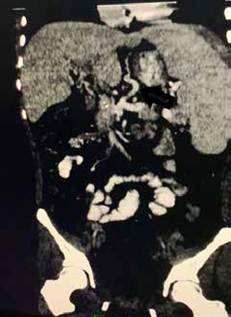

Al ingreso se documentó hiperesplenismo con trombocotipenia (17.000 plaquetas por mcL) y esplenomegalia, se realizó una tomografía abdominal donde se observó una degeneración cavernomatosa de la porta y esplenomegalia masiva (figura 3). Por los episodios de sangrado frecuente y el hiperesplenismo, se decidió llevar a derivación meso-Rex, pero de forma preoperatoria bajo anestesia general se realizaron dos sesiones de embolización esplénica con coils y onyx, con el objetivo de mejorar el recuento de plaquetas y de disminuir el tamaño del bazo, para así lograr preservarlo (figuras 4a y 4b), logrando aumentar el recuento plaquetario a 192.500 por mcL.